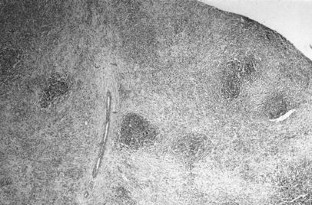

Fig. 1

Fig. 2

Fig. 3

Fig. 4